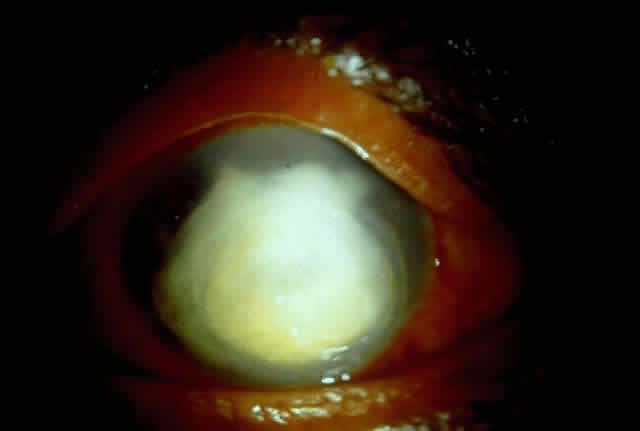

Active corneal infections in advanced stages are encountered more often by corneal surgeons in developing countries compared with their counterparts in developed countries (Fig. 8). The extent of corneal involvement associated with other intraocular damage often compromises the success of corneal transplantation. In a series from our institution, the success rate for graft clarity was poorer24 compared with other series.25 Ophthalmologists involved in corneal surgery should be familiar with this information and be prepared for the necessary intraoperative manipulations (Fig. 9).

Fig. 8. Corneal ulcer with extensive necrosis and perforation in the superior part.

Fig. 9. Large central perforation in a case of infectious keratitis.